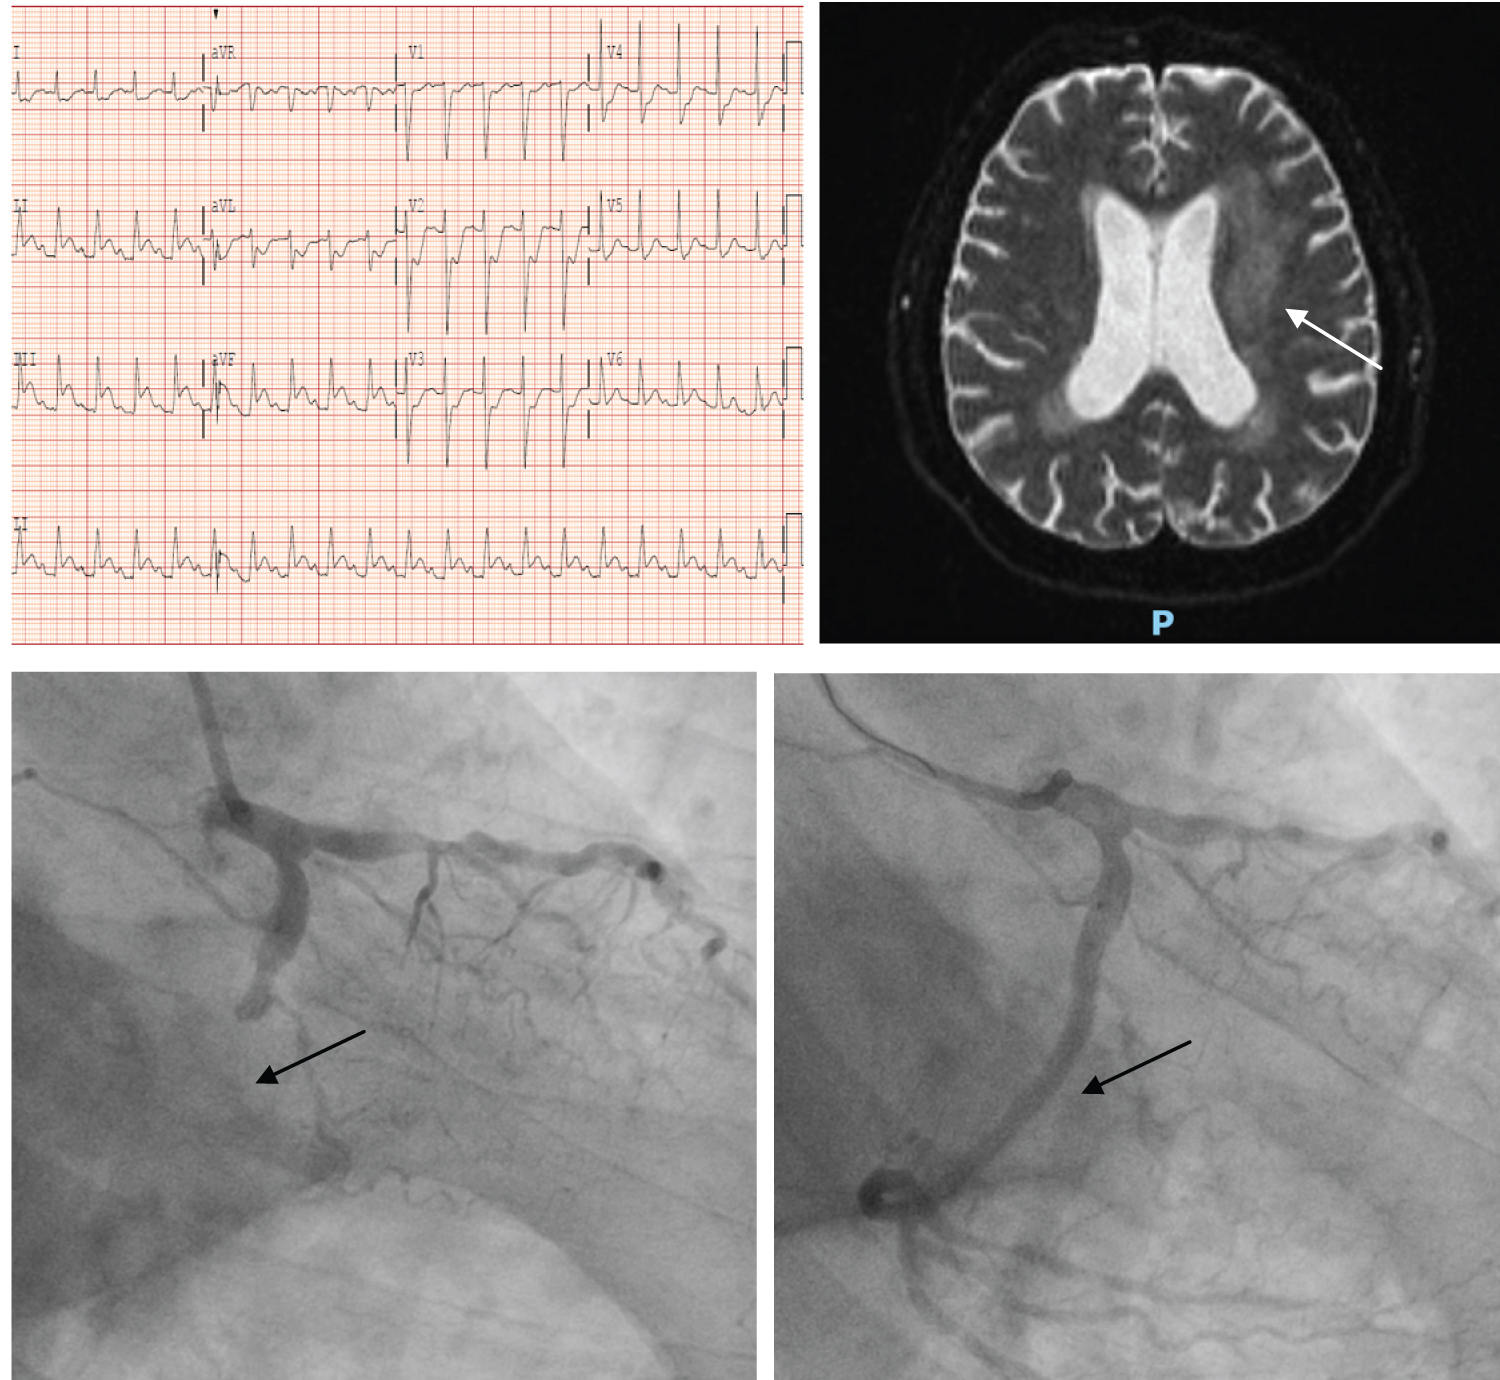

An 80-year-old man was admitted for persistent vertigo. He had past medical history of diabetes, hypertension and hyperlipidemia. Examination revealed weakness in his left sided limbs. Urgent CT brain showed possible acute infarct in the right precentral gyrus. MRI brain showed small, scattered acute infarcts in the bilateral frontal lobes with mild petechial haemorrhagic conversion. On the same day evening, he complained of new onset chest discomfort with breathlessness. ECG showed inferior posterior STEMI. There was a new finding of bibasal lungs crepitation. After discussion with the patient and medical team, a decision was made to proceed with emergency coronary angiogram keeping in mind the risk of worsening hemorrhagic conversion. Successful PCI was performed to an occluded right coronary artery with a single DES (Resolute Onyx 3.5 × 38). In addition, he was found to have atrial fibrillation and therefore started on short term 1 month triple therapy (DAPT + NOAC) with plan for down titration to long term dual therapy (clopidogrel + NOAC). His echocardiogram showed LVEF of 35%. His initial neurological deficits gradually resolved during his hospital stay without clinical findings to suggest deterioration of initial cerebral haemorrhagic conversion. He was discharged from hospital on day 8 of hospitalisation (Figure 3A, Figure 3B and Figure 3C).

Figure 3: (A) ECG showed inferior ST elevation with reciprocal ST depression; (B) MRI brain showed mild petechial haemorrhagic conversion within one of the infarcts in the right frontal operculum; (C) Angiographic findings of before and after proximal right coronary artery stenting. View Figure 3